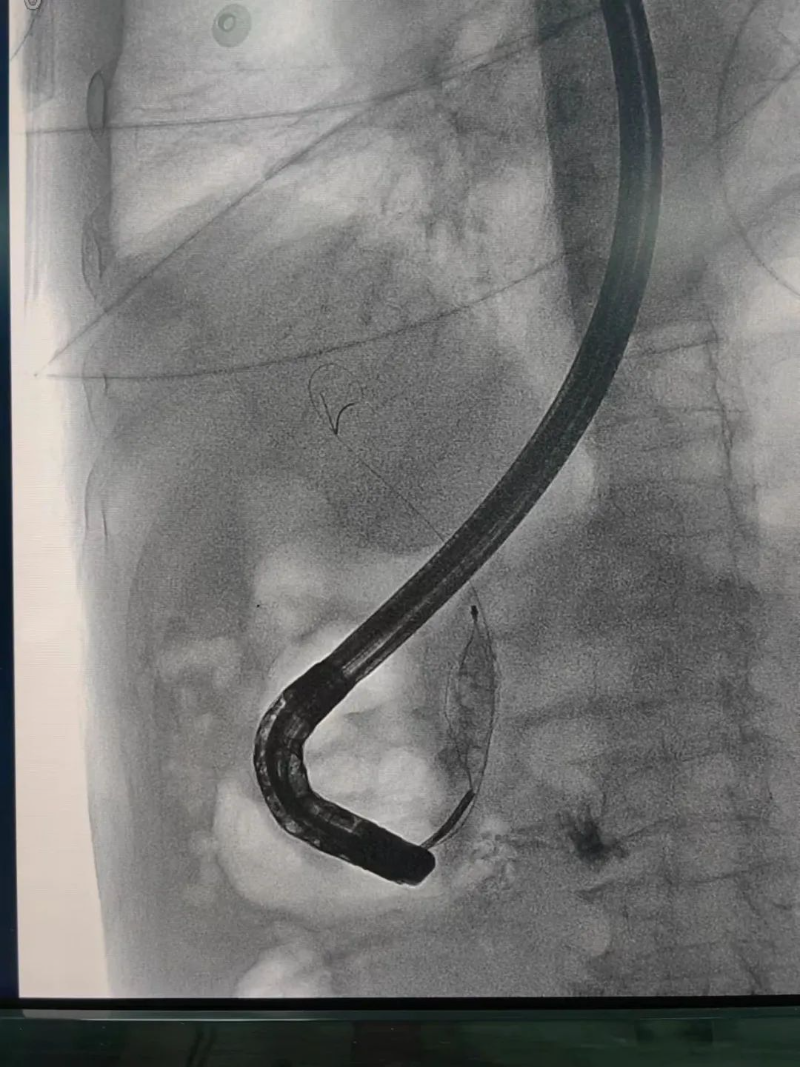

经内镜逆行胰胆管造影术(以下简称ERCP)是治疗胆管结石的首选方法,ERCP属于介入和微创手术,可以有效减少传统手术对患者身体的创伤,能快速缓解临床症状,降低相应并发症的发生,改善肝功能,促进患者康复、减少围术期应激,缩短住院时间,是项较安全、直观、可靠的治疗手段,对肝胆、胰疾病有较高的诊断和治疗价值。

ERCP是经口内镜胆道治疗技术。是国际公认的胆管胰腺系统疾病诊断的金标准,是确诊胆管结石的最佳方法。在ERCP基础上,可以同时进行胆总管结石取石术、Oddis括约肌切开术、胆总管支架植入术、鼻胆汁引流术等微创手术,对胆总管结石等疾病进行安全、快速、有效的治疗。